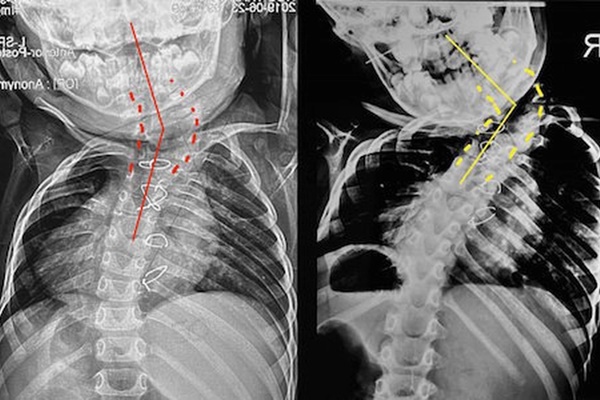

Phim chụp X-quang của bệnh nhi sau 3 năm không được điều trị kịp thời. Ảnh: BVCC

Năm 2019, gia đình đưa bệnh nhi đến Bệnh viện Đại học Y Hà Nội khám và được chẩn đoán vẹo cột sống bẩm sinh do bất thường phân đoạn và bất thường hình thành cấu trúc thân đốt sống. Tình trạng này khiến cho toàn bộ cột sống vùng cổ và ngực bệnh nhi bị biến dạng vẹo lệch sang bên trái.

Do đang trong quá trình tiến triển của đường cong, nên bệnh nhi có chỉ định theo dõi sự biến dạng bằng cách chụp X-quang sau mỗi 6 tháng, nhằm bắt được giai đoạn tăng trường bất thường thì sẽ có chỉ định can thiệp phẫu thuật.

Bệnh nhi bị vẹo cột sống lệch hẳn sang bên trái.